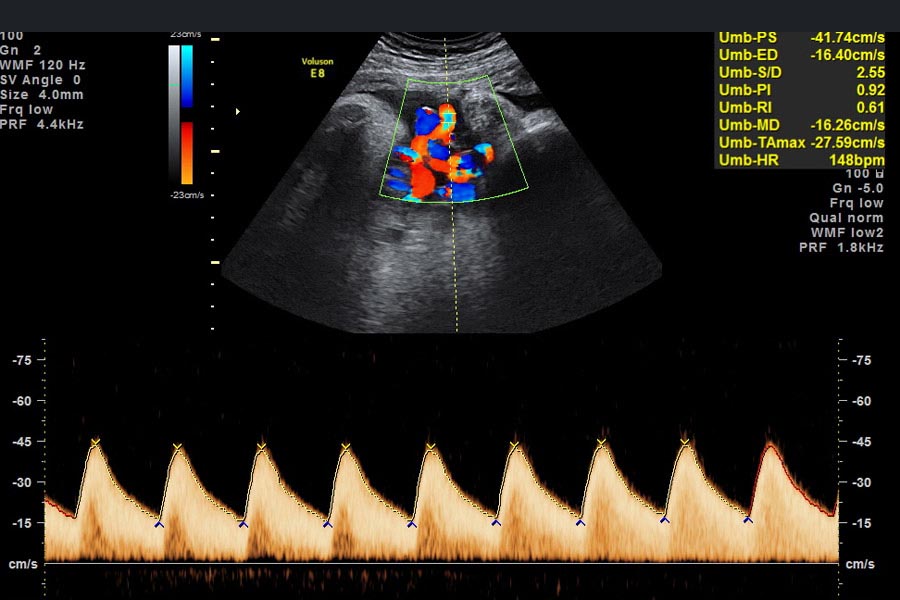

Die Dopplersonographie ist eine spezielle Form des Ultraschalls. Mit der Dopplersonographie, benannt nach deren Erfinder, dem Physiker Christian Doppler, lässt sich die Durchblutung der kindlichen Gefäße, in der Nabelschnur und in den Gebärmutterarterien messen und das Blutflussmuster analysieren.

Sie wird in erster Line dann empfohlen, wenn eine Unterversorgung des ungeborenen Kindes, beispielsweise aufgrund einer Leistungsschwäche der Plazenta, die den Stoffaustausch zwischen Mutter und Kind beeinträchtigt, ausgeschlossen werden soll. Oder aber bei Auffälligkeiten der kindlichen Herzfrequenz, bei Verdacht auf Fehlbildungen des Kindes, bei Mehrlingsschwangerschaften oder Verdacht auf Herzfehler oder -erkrankungen.